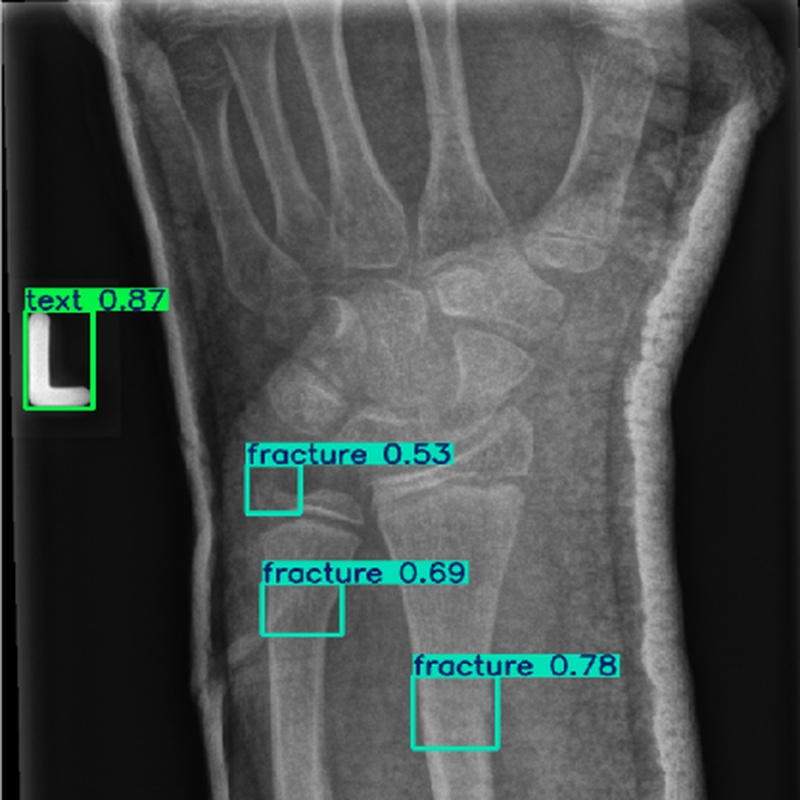

现场环境 在医学成像环境中,使用X射线、CT或MRI等设备获取图像。图像采集过程中可能存在噪声干扰,且骨折目标通常较小,仅占图像像素的2.3%左右,需要在低对比度和复杂背景的条件下进行检测。

使用对象 医学图像中的骨折区域,包括不同类型的骨折(如骨异常、骨损伤等),尤其是小目标骨折区域。

输出数据 骨折检测结果,包括骨折区域的边界框坐标、类别标签(如骨折、金属等)以及置信度。

测试结果 在测试集上,ASC-YOLO模型实现了61.1%的mAP@50,比基线YOLO模型提高了7.4%。断裂类别的mAP@50达到95%,金属类别的mAP@50达到97%。